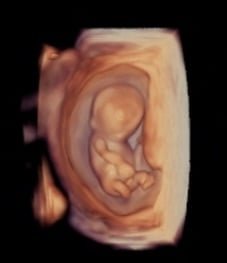

kombiniertes Ersttrimesterscreening mit Risikoberechnung für früh in der Schwangerschaft auftretende Bluthochdruckkomplikationen sowie die häufigsten Chromosomenstörungen beim Kind zwischen 11+0 – 13+6 SSW. Diese Untersuchung beinhaltet immer auch eine frühe Fehlbildungsdiagnostik des Kindes.

Ich arbeite mit einem „High-End-Ultraschallgerät“ der neuesten Generation, welches speziell für Pränataldiagnostik und Frauenheilkunde entwickelt wurde.